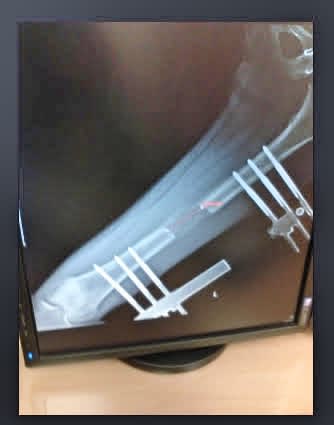

The surgeries did not just involve cutting the bones. Sometimes I had to lengthen bones to stop my limbs from curving too much.All my life, I was afraid to push myself physically. I worried that the racing heartbeat would continue forever. My body was very inflexible; I could not put on socks alone. While recovering from the surgeries, I would miss school for months. When I returned, I would sit out during PE classes and watch my classmates play sports. I was a “walking hospital,” as my PE teacher said.

In the Summer of 2008, after graduating from high school, I did another round of surgery to remove bones in my legs and chest. We did a full body scan to ensure nothing was left behind, and a CT scan revealed a large bone tumor on the right pelvis, which had pushed my spine to the left and caused scoliosis. The doctor determined that removing the bone would significantly alleviate the back pain. I was thrilled I could finally live without pain. But the night before the surgery, he came to my room to explain the chance that I might lose control of my right peroneal nerve after the surgery since the tumor sat very close to the spinal nerve. For the rest of the night, I dreaded imagining what it would be like wearing a support device to walk. Luckily, the surgery went very successfully. As soon as I woke from anesthesia, I tried to rotate my right ankle. I could move it.

I entered rehab for a month. I slept while hanging on pulleys with weights to stretch my spine. The increased pain came from my right back, which used to be supported by the bone and did not have muscles to support the right side. I learned rehab exercises to combat this issue and wore a brace covering my entire torso to support it and to prevent my spine from curving more.